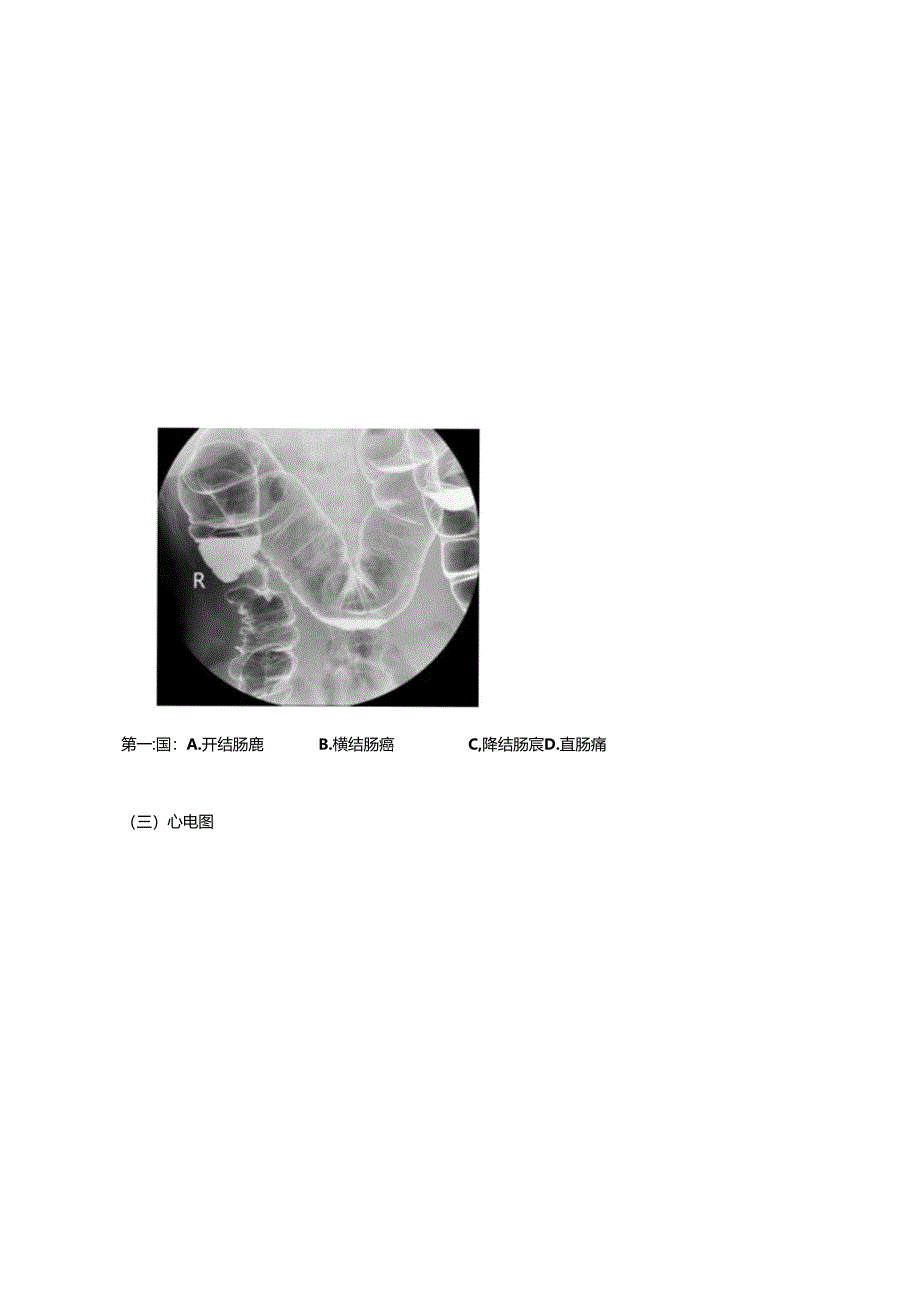

2015技能模拟临床执业第一套第三站试题卡第三站计算机多媒体考试心肺听诊(兄录青文件111-2)I.肺部听诊C胸膜摩擦音B.舒张中期春马律D.舒张早期奔马律D.干罗音A.*鼻音H.水泡音2.心脏听诊A.舒张期隆隆样杂音C.舒张晚期奔马律二)Xac执业笫一趟:A.硬脑胶外出血B.脑出血C.脑梗死D硬脑脱下出血第二区A.浸润型肺结核B.右侧肺炎C.右侧肺癌D.气胸第一:国:A.开结肠鹿B.横结肠癌C,降结肠宸D.直肠痛(三)心电图第题.诉性期前收缩B.:废I型居室传峥阻滞C.Ji(II型房室传导阻滞D.三度房室传导阻滞第二期A.正常心电图C.下壁心肌梗死B.左心室肥厚D.心肌缺血(四)医德医风患者,男性,6()岁.发现自己的尿液为红色来院就诊,医生羟过问诊后安排尿液化验.但是.患者就诊前担心自己的病怙严重,副间过有关医学的籍,担心自己患有泌尿系肿痛,询问医生精情严重程度,面对患齐的询问,作为他的主治医师,您应该怎样回答该患者?A.实话实说.诚实的面对患者.让患者接受现实.B.先安慰强齐.稔定患荷情绪.然后把实情告诉患者家属,针对患齐病情通知上级医生.C.在SJ者面前保持沉蚊,把检住结果只告诉患者家属.D.向患者I瞒病情,知为一微炎症导致.